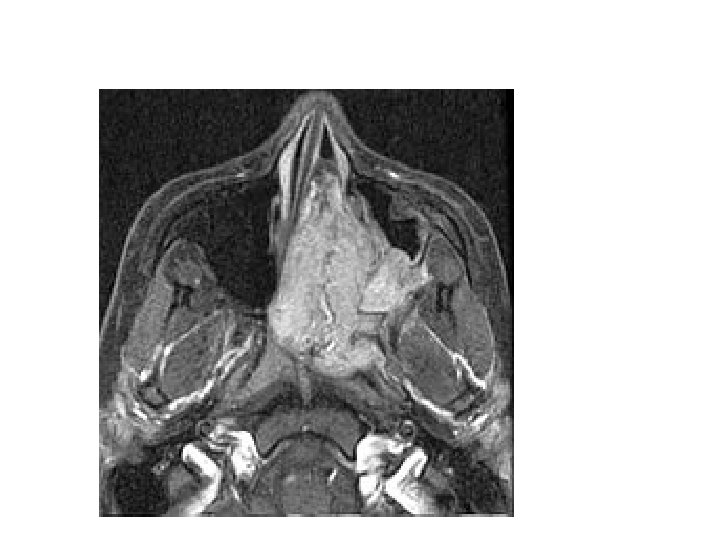

PAPILOMA NASAL INVERTIDO: • Primer caso descrito por Ward en 1854. • Papiloma de células cilíndricas. • Inversión del epitelio neoplásico dentro del estroma subyacente en lugar de proliferación hacia fuera. • Frecuencia entre todos los tumores de nariz y senos paranasales 0. 5 - 4%

PAPILOMA NASAL INVERTIDO: • Grupos de edad: 50 - 70 años, predominando en sexo masculino 3: 1. • Virus papiloma humano 11 y 16.

PAPILOMA NASAL INVERTIDO: • Clasificación: • T 1: confinado a cavidad nasal sin extensión paranasal. • T 2: afecta al complejo osteomeatal y al seno etmoidal o a la porción media del seno maxilar. • T 3: afecta paredes lateral, inferior, superior, anterior o posterior del seno maxilar, seno esfenoidal o seno frontal. • T 4: extensión extranasal o extrasinusal y cualquier tumor asociado a malignidad.

• • Clínica: Obstrucción nasal unilaterla (97%). Cefalea (33%). Rinorrea mucosa (30%). Epistaxis (9%). Hiposmia (9%). Dolor facial (6%).

PAPILOMA NASAL INVERTIDO: • Macroscopicamente: • Semejante a pólipo, tumoración grisácea o rosada, lobulada y friable. • Microscopicamente: • A)invertido. • B)fungiforme. • C)Cilindrico.

PAPILOMA NASAL INVERTIDO: • Tratamiento: • Qurirugico, con alto indice de recurrencia con extirpacion incompleta. • Las mas comun es la sublabial. • Nuevas tecnicas: Endoscopica.